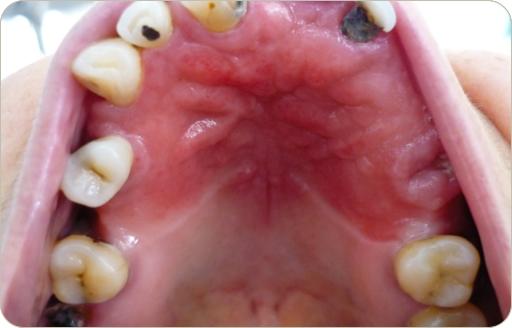

En este mes tenemos tres casos, dos son clínicos y uno es radiográfico, esperamos tu participacion al correo patobu1@hotmail.com o